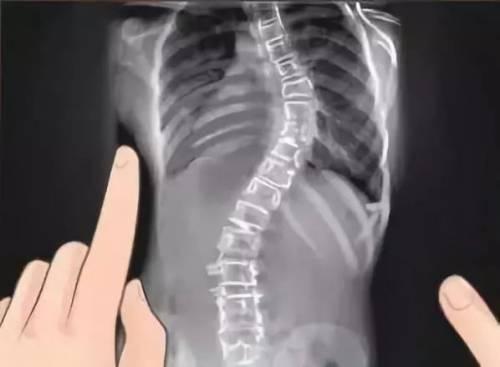

小孩的脊椎也是很重要的部位,如果不好好矫正姿势的话很可能就会出现脊椎侧弯,严重的话甚至要开刀治疗。要有正常的发展首要任务就是要维持优良姿势,并不是长大后再调就好,要从小养成良好姿势!下面的小编为大家分享如何预防婴儿脊柱侧弯,怎么让宝宝脊椎正常发育大家一起来看吧。

当宝宝会自己移动时,你应该让他维持正确的姿势,不论是坐着或站着。姿势不良不仅会影响成人,对骨骼还在发展的婴幼儿危害更大。

不良的姿势会导致脊椎弯曲、生长异常。因此,你应该要协助孩子保持良好的姿势,像是准备合适的书桌椅、减少3C产品使用量、优质的床垫等等。